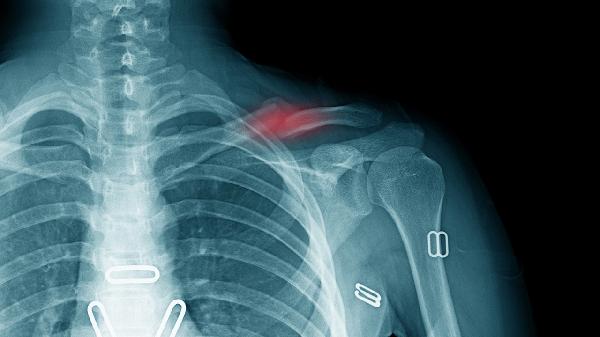

青少年骨骼快速生长期间,骺板软骨内成骨过程出现紊乱可能形成囊肿。这种发育性囊肿好发于肱骨近端和股骨远端,X线可见边界清晰的透亮区。若无病理性骨折风险,可观察随访;若囊肿持续扩大,需考虑注射醋酸甲泼尼龙混悬液等药物或行病灶刮除术。